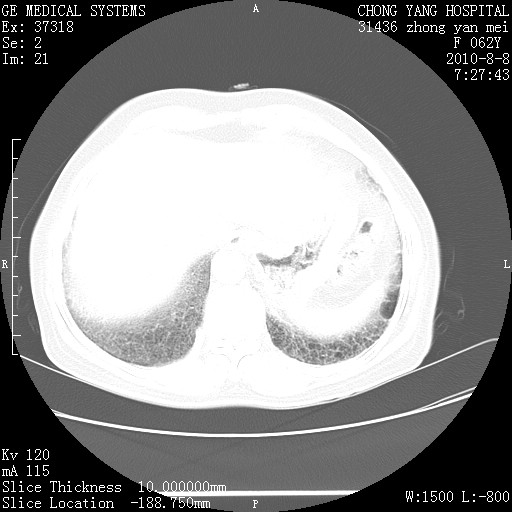

标题: CT28269:F62Y咳嗽胸痛数月。 [打印本页]

标题: CT28269:F62Y咳嗽胸痛数月。

两肺弥漫性间质纤维化伴继发性支扩。

考虑特发性肺间质纤维化

考虑两肺间质性肺炎并肺间质纤维化。

肺间质纤维化合并感染

双肺间质纤维化合并感染、肺气肿

双肺间质纤维化

特发性的肺间质纤维化

另见右乳腺似有小钙化灶,建议进一步检查。

特发性肺间质纤维化合并感染!

1.肺间质纤维化.

2.纵隔淋巴结肿大。

3.迷走右锁骨下动脉。

两肺间质纤维化并牵拉性细支气管扩张。

考虑两肺间质性肺炎并肺间质纤维化,肺气囊形成。

两肺间质改变,纵隔淋巴结肿大,需要考虑结节病的可能。